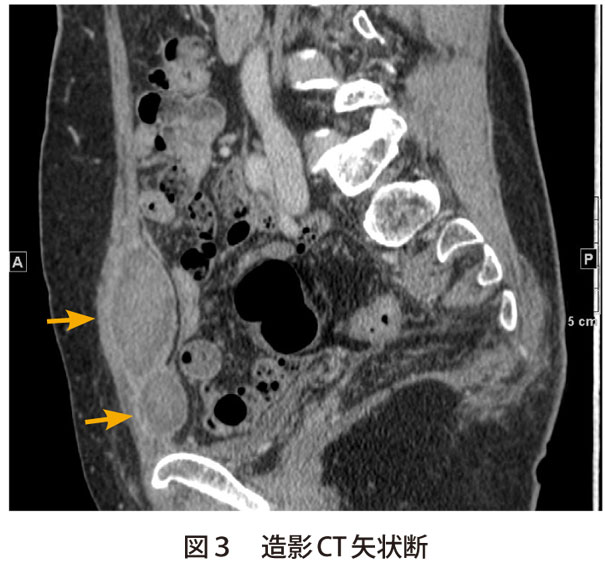

疾患の概要 サッカーなどのスポーツを中心に、鼠径部周辺には多様な原因で発生する各種の痛みがあり、本当の原因を特定しにくいため鼠径部痛症候群(Groin pain syndrome、図)と述べています。 鑑別障害に恥骨結合炎、大腿内転筋付着部炎、大腿直筋炎、腹直筋付着部炎、腸腰筋炎、鼠径ヘルニア(スポーツヘルニア)などが挙げられます。 図 鼠径部周辺の疼痛 腹壁の知覚はTh7–12の脊髄神経前皮枝と外側皮枝により成り立っており,腹直筋の部位で前皮枝が絞扼されるとACNESを生じる.近年,本邦での報告が増加している(表2).発症要因は特発性(57%),最近の腹部手術歴(28%),事故やスポーツ外傷,妊娠等であり 7) ,①血液や画像検査で異常がない,②腹直筋外縁2 cm 2 の範囲に限局した圧痛,③Carnett徴候 非外傷性腹直筋血腫とは? その本体は急激な腹直筋収縮や過伸展に伴う筋断裂や下腹壁動脈の破綻による血腫形成と考えられている。 腹直筋血腫、腹直筋鞘血腫、腹直筋症候群などと呼ばれることがある。 原因としては、呼吸器疾患に伴う

腹直筋鞘血腫 Rectus Sheath Hematoma 医學事始 いがくことはじめ